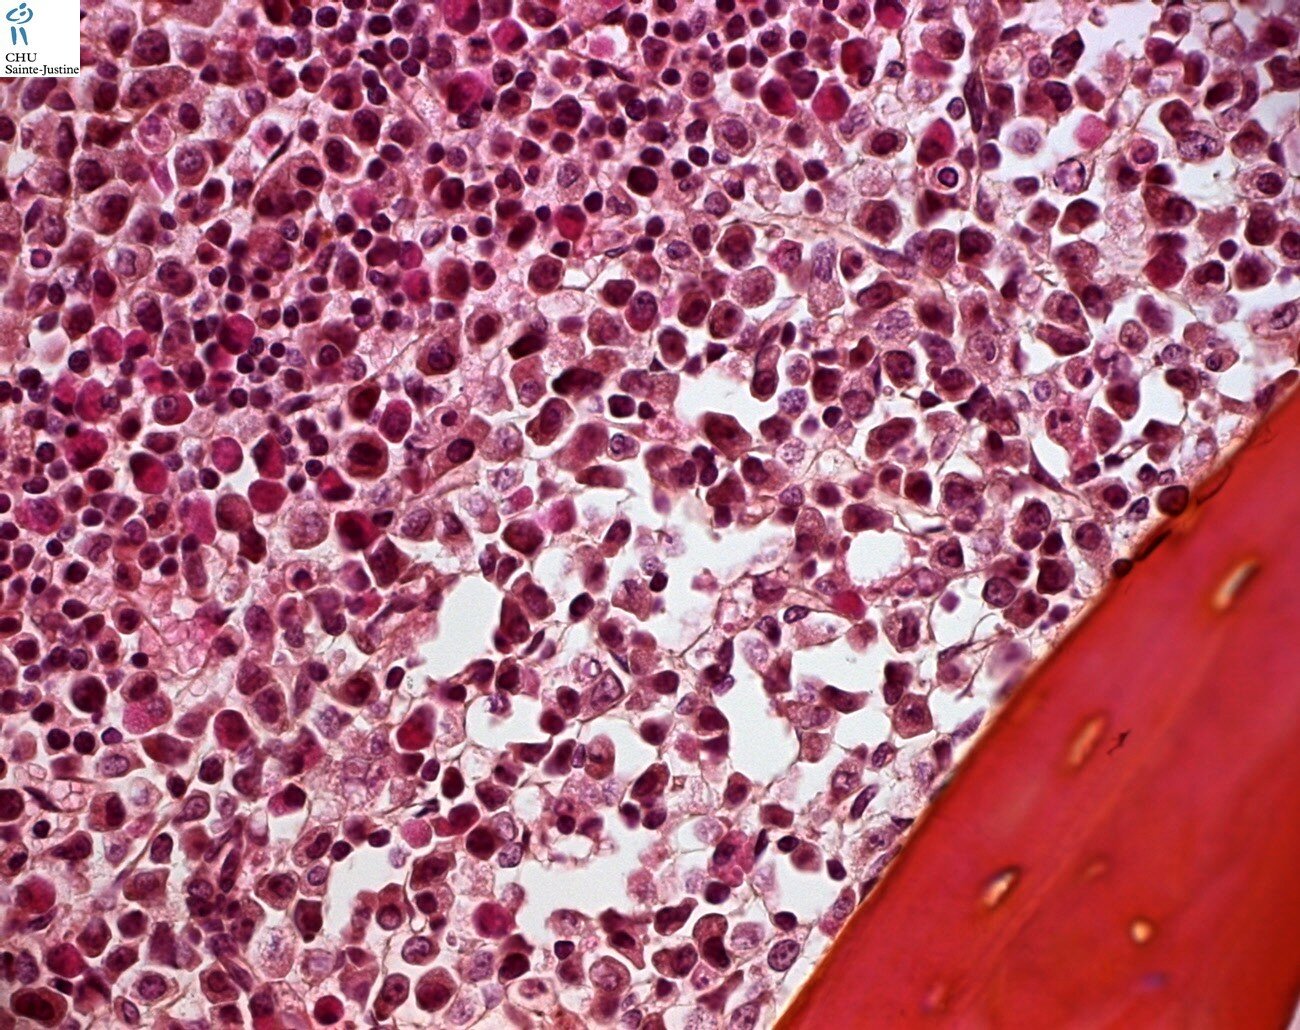

Morphology